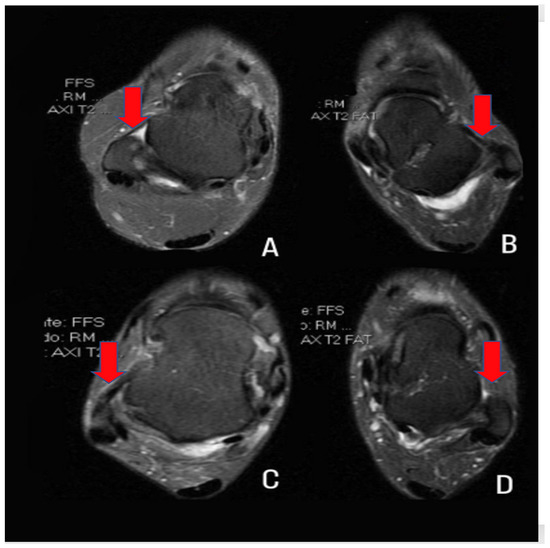

2.3. Computational Characterization of the ATFL

2.4. Description of the Database

2.5. Data Extraction